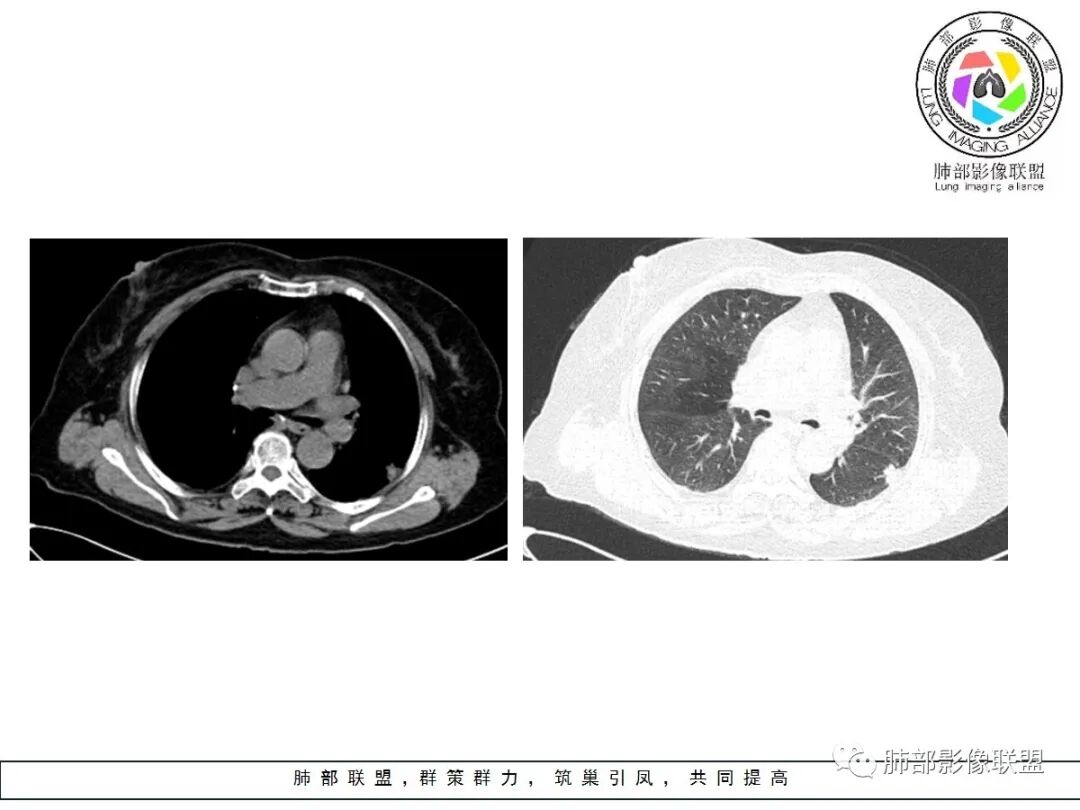

病例资料

左肺下叶的不规则病灶,有恶性征象,有深分叶,病灶有支气管进入截断了,病灶里支气管扩张;良性征象有平直征,病灶强化明显,脂肪间隙存在,肉芽肿病变鉴别肌纤维母细胞瘤

老年女性,左肺下叶的不规则病灶,深分叶,病灶有支气管进入截断,血管集束,斜裂牵拉,但胸膜干净,有平直征,病灶强化明显,最后还是考虑恶性,鉴别隐球

左肺下叶背段胸膜下不规则结节,有良性征象:有平直、U形凹陷,胸膜下脂肪间隙清晰,明显强化;又有些恶性征象:有分叶,叶间胸膜牵拉。

有些纠结,还是考虑恶性(腺癌可能)> 炎性肉芽肿

良性征象(宽基底与胸膜相连,没有明显胸膜凹陷与微积液,收缩力较弱,仅仅叶间胸膜略凹陷,边缘平直,U形凹陷为主,结节较散,增强动脉期强化太明显)>恶性征象(局部略有膨隆,叶间胸膜略凹陷),可疑征象(图像不太好,支气管截断不确定,分叶征象不确定,也可能是散在结节的假象,脐凹征可疑),综合考虑良性结节可能大(隐球?结核?其他炎性结节?局部肺栓塞?)腺癌待排,临床简单,穿刺一下就OK。

左肺下叶胸膜下结节,边缘部分平直收缩部分膨隆,可疑脐凹征,邻近叶间裂稍牵拉,胸膜糊墙,增强扫描均匀强化,老年女性,良恶性征象都有,平扫密度似略偏高,先考虑良性,隐球菌?一般炎性肉芽肿?腺癌待排,老年人,警惕性提高一个级别,治疗后复查或穿刺活检。

一、本例恶性征象较有特征的是脐凹征。

1.脐凹征:分叶状结节局部凹陷的部位受到血管阻力而形成,表现为血管进入分叶之间,脐凹相对比较对称光滑,近肺门侧多见,与血管走行方向一致。

2.95%见于恶性肿瘤,5%为炎性病变。

3.病灶显著强化不支持结核;边界清楚,肺门一侧波浪状改变,患者为老年女性,缺乏临床表现,尽管影像有一些炎性灶特点,但恶性肿瘤性病变不能除外。